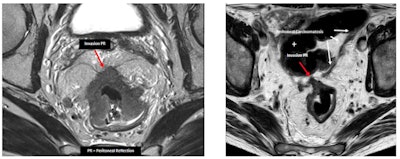

"Differentiating T2 tumors from early T3 tumors can be difficult. A spiculated desmoplastic reaction in the perirectal fat or peritumoral inflammation may mimic tumor involvement. However, T2 and early T3 have the same prognosis," the authors wrote. "In peritonealized portions of the rectum (proximal), the tumor can be staged as T4a and does not represent carcinomatosis."

Serosal involvement does not necessarily represent peritoneal carcinomatosis. In peritonealized portions of the rectum (proximal), tumor can be staged as T4a and does not represent carcinomatosis. These tumors have a significantly higher risk of carcinomatosis (M1c stage). This group of patients might be eligible for new treatment strategies that aim to treat in an earlier or even preventive setting. (PR = peritoneal reflection)In rectal cancer surgery, surgeons have to ligate the inferior mesenteric artery, and they can opt for a high or low ligation (preserving the left colic artery). A good description of the vascular anatomy brings safety to the surgery and can help the surgeon in his decision-making, they explained.